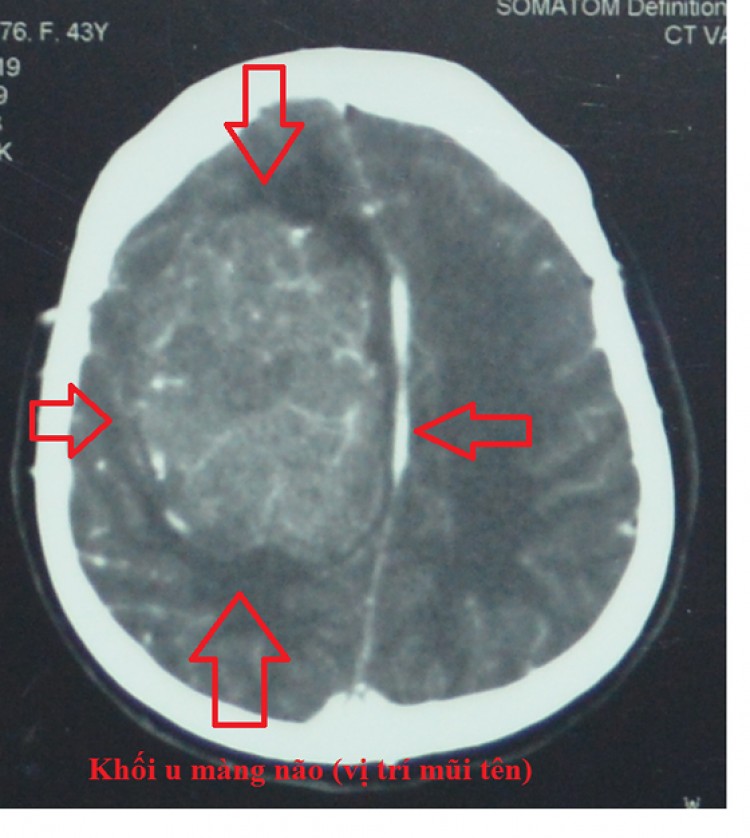

Ngay khi nhập viện, các bác sĩ tiến hành thăm khám và kiểm tra, kết quả cho thấy bệnh nhân bị u màng não bên phải với kích thước 5x8cm. Với tình trạng động kinh, diễn biến phức tạp nên nguy cơ trong và sau mổ rất cao do khối u nằm ở vị trí vùng vận động. Bệnh nhân có thể liệt tay, chân, nếu không xử trí tốt.

Khối u màng não rất lớn, nguy hiểm